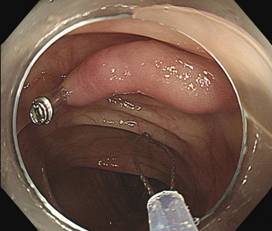

在与陈先生阐明病情后,医生采用套扎术切除

钛夹阻断血流,准备直接圈套,圈套切除,息肉离体以及创面